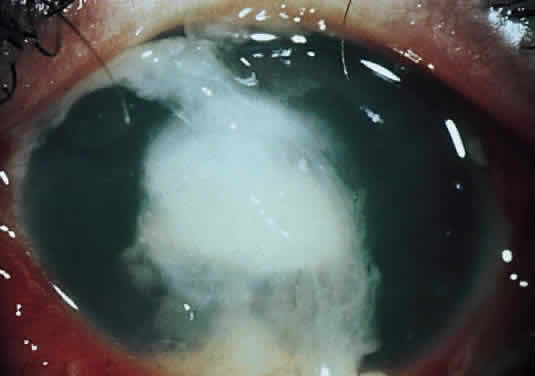

Corneal ulcers caused by S. pneumoniae are typically described as serpiginous or creeping and most often spread toward the center of the cornea. They are characterized by a gray-yellow disc-shaped ulcer with an overhanging margin at the advancing edge (Fig. 5). The ulcer usually progresses rapidly, extending into the deep stroma and often leading to corneal perforation. Extensive damage to corneal tissue, as well as a characteristic sterile hypopyon, are caused by the rapid production of bacterial exotoxin within the stroma.40,41

Fig. 5. Large, disk-shaped corneal ulcer caused by Streptococcus pneumoniae in an elderly woman. The presence of a sterile hypopyon is often associated with these ulcers.